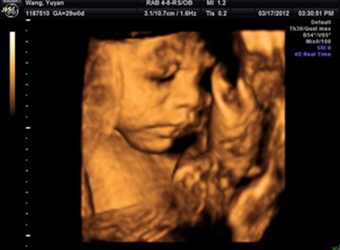

四维超声是一种比较先进的检查方式,也是实时的动态三维超声,一般来说通过四维超声来辨别宝宝性别是比较准确的,四维单子上出现了四个字的就是怀了男宝,更多…